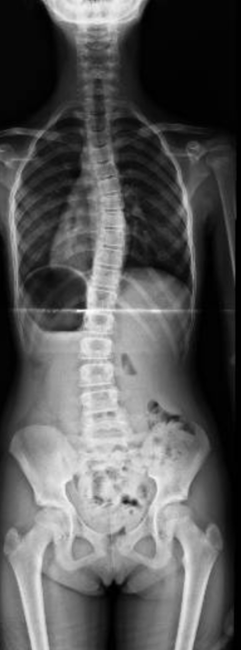

Morena

Inicio del tratamiento:

2018

Edad de la paciente:

10 años

Patología:

Escoliosis Idiopática del Adolescente.

Tratamiento: Uso de un corsé, y ejercicios indicados para prevenir la progresión de la curvatura. Al año: la escoliosis y el valor angular empeoraron significativamente En la primavera del 2020, plena pandemia, se llevó a cabo la corrección quirúrgica. Hoy, Morena ha logrado retomar sus actividades y actualmente juega al hockey. Su evolución refleja cómo, a pesar de las dificultades, se puede avanzar en el tratamiento de la escoliosis.